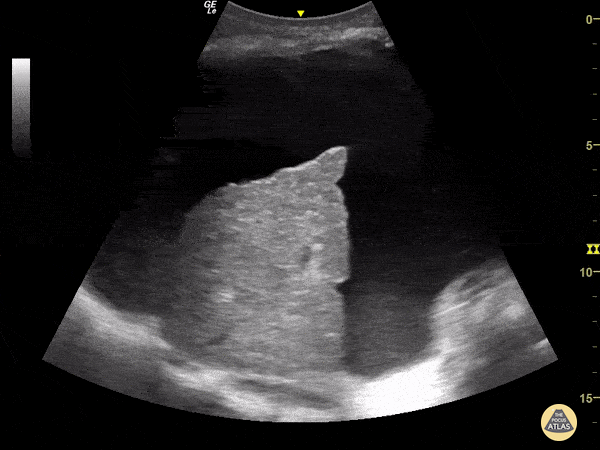

70-year-old man with a history of alcoholic liver cirrhosis. This RUQ view obtained with a curvilinear probe reveals a cirrhotic liver (reduced dimensions with irregular edges and an overall heterogenous echotexture) surrounded by significant ascites within Morison's Pouch. Renato Tambelli, Emergency Physician Hospital das Clínicas de Marília.Public Healthcare @R_Tambelli